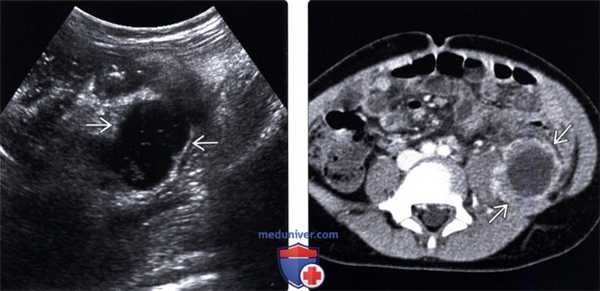

4. УЗИ внутрибрюшного абсцесса:

• Неоднородное скопление жидкости с включениями невысокой эхогенности, с наличием перегородок, септ, или многокамерное: о Эхогенные включения отражают наличие дебриса в абсцессе:

- Усложнение структуры абсцесса предполагает наличие более густого, вязкого содержимого

- Комплексная структура абсцесса при УЗИ предполагает затруднения при его дренировании (особенно при помощи тонкого катетера)

2. УЗИ при абсцессе брюшной полости:

• Серошкальное исследование:

о Сложное скопление жидкости, содержащее источники низкоинтенсивных сигналов, мембраны или перегородки

о Оседающие книзу источники эхосигналов представляют собой детрит и могут формировать уровень жидкость-жидкость

о Яркие линейные эхосигналы, сопровождающиеся реверберационными артефактами, представляют собой пузырьки газа; такая картина очень характерна для инфекции о Прилегающая к абсцессу воспаленная жировая клетчатка отображается как эхогенное образование: